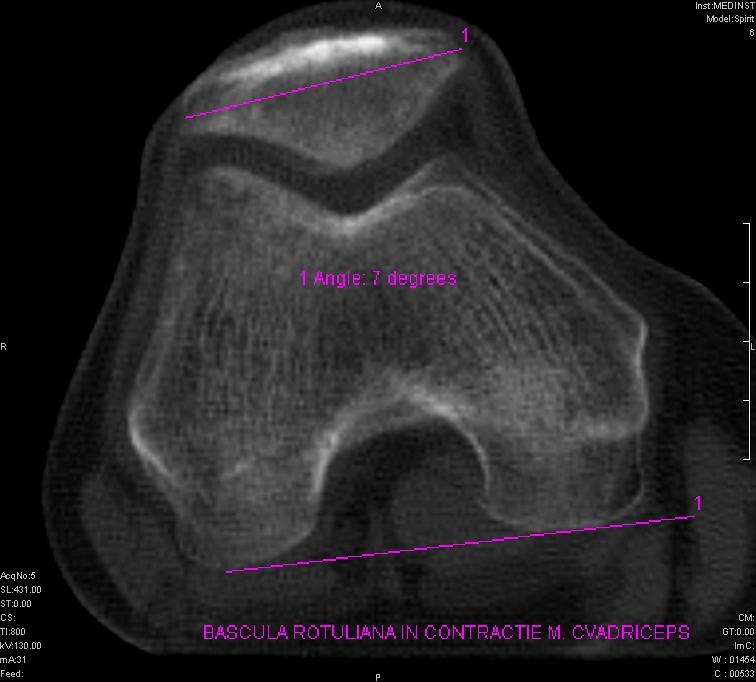

- măsuratori de stabilitate rotuliană;